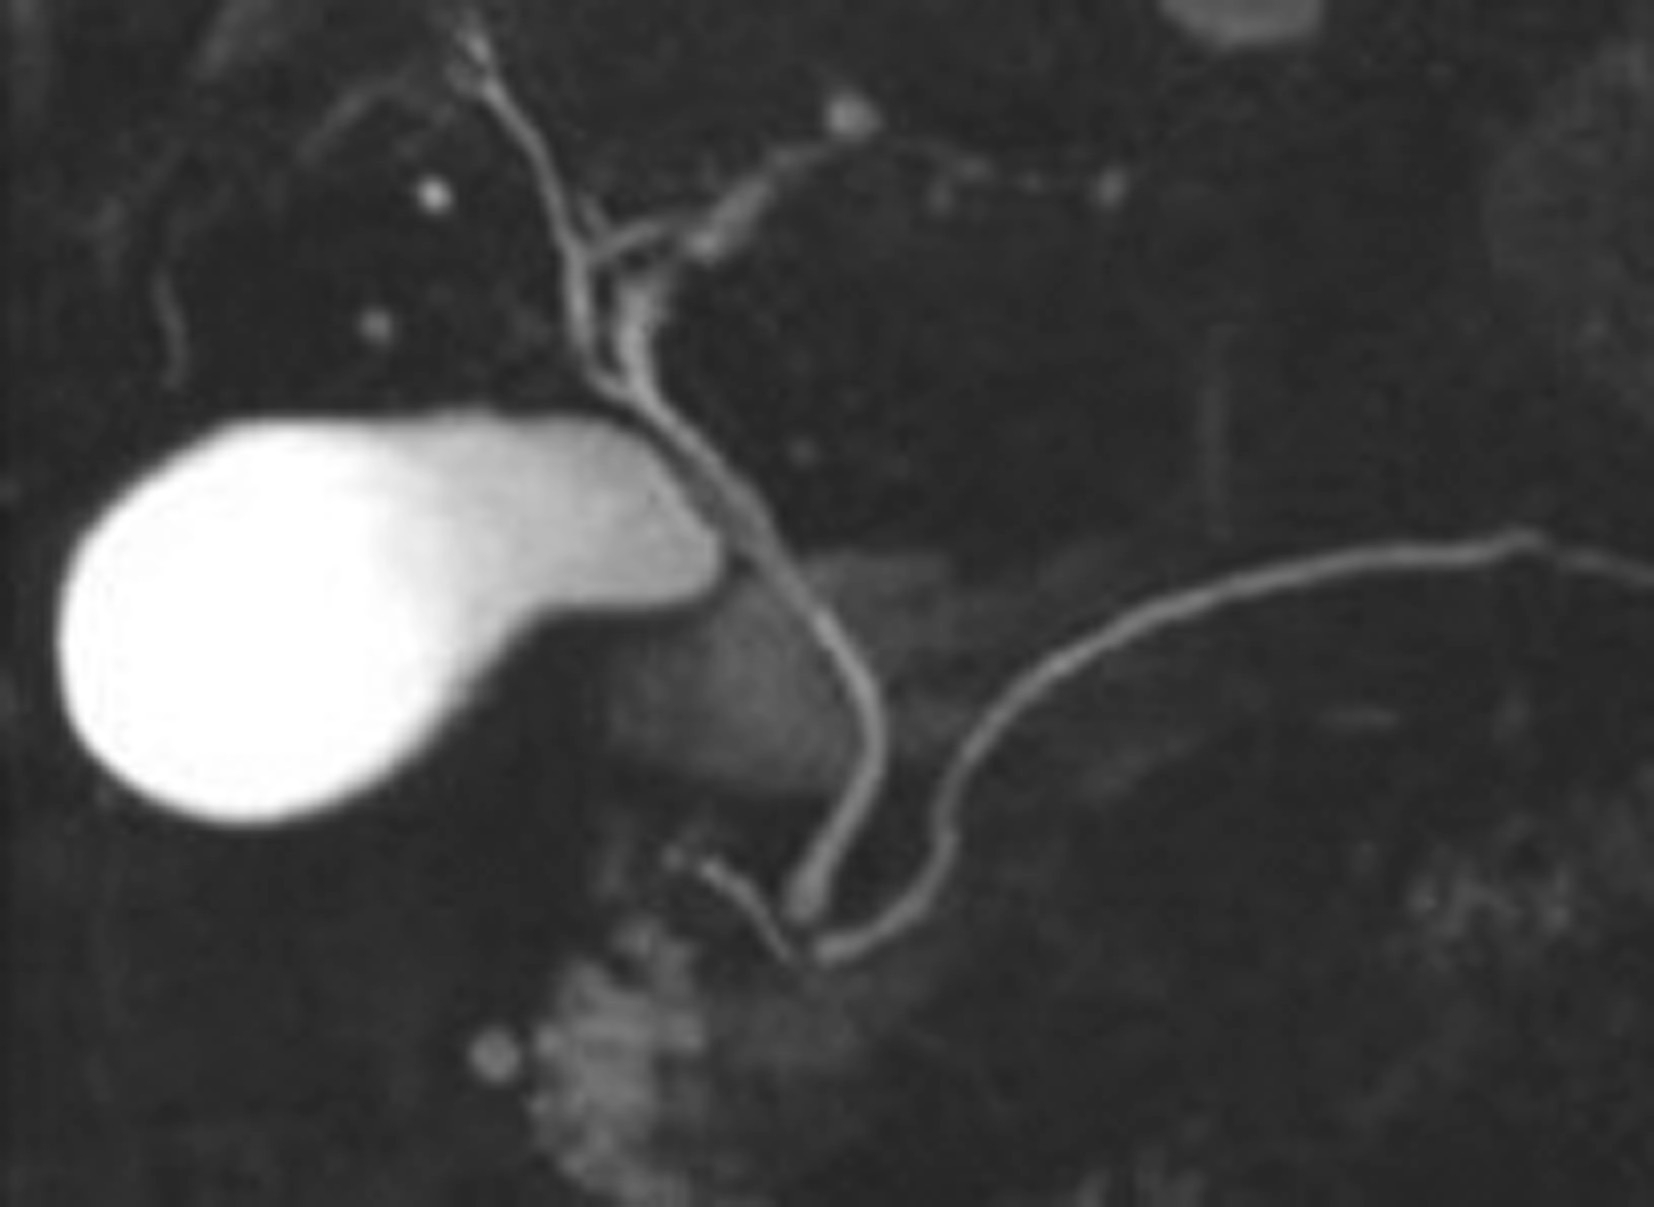

内镜逆行胰胆管造影(endoscopic retrograde cholangiopancreatography,ERCP)指将十二指肠镜插至十二指肠降部,找到十二指肠乳头,由活检管道内插入造影导管至乳头开口部,注入造影剂后进行X线透视和摄片,以显示胰胆管的技术。临床上是显示胰胆管的主要方法之一。它使成像的胆管系统可达到最大可能的范围,若插管成功,注入造影剂,可见内镜逆行胰胆管造影(图5-21-45)。同时可以进行各种治疗程序。如胆总管结石的诊疗中,以往需要外科手术治疗,存在手术创伤大、术后恢复慢、结石残余或复发等难题。在采用ERCP后只需通过十二指肠乳头小切口,即可对肝外胆管结石(图5-21-46)进行碎石、取石、清理等操作。ERCP最早的报道在1968年,随着器械和技术的进步,而在临床上得到推广应用。目前,临床上应用ERCP并不是单纯为了诊断胆管系统的疾病,因为已有了更微创和有效的手段,如磁共振胰胆管成像(magnetic resonance cholangiopancreatography,MRCP)和超声内镜(endoscopic ultrasound,EUS),而主要应用在处理胆道的疾病。适应证主要有胆道梗阻引起的黄疸,如急性胆管炎、胆总管结石、胆道狭窄、胆漏、胆道出血和Oddi括约肌功能紊乱等。内脏穿孔为绝对禁忌证,凝血功能异常、无并发症的急性胰腺炎和心肌梗死都是相对禁忌证。以下简述其技术方法:

图5-21-45 内镜逆行胰胆管造影法示胰胆管

可见胆囊及胆系树枝状影像,并清晰显示胰管走行